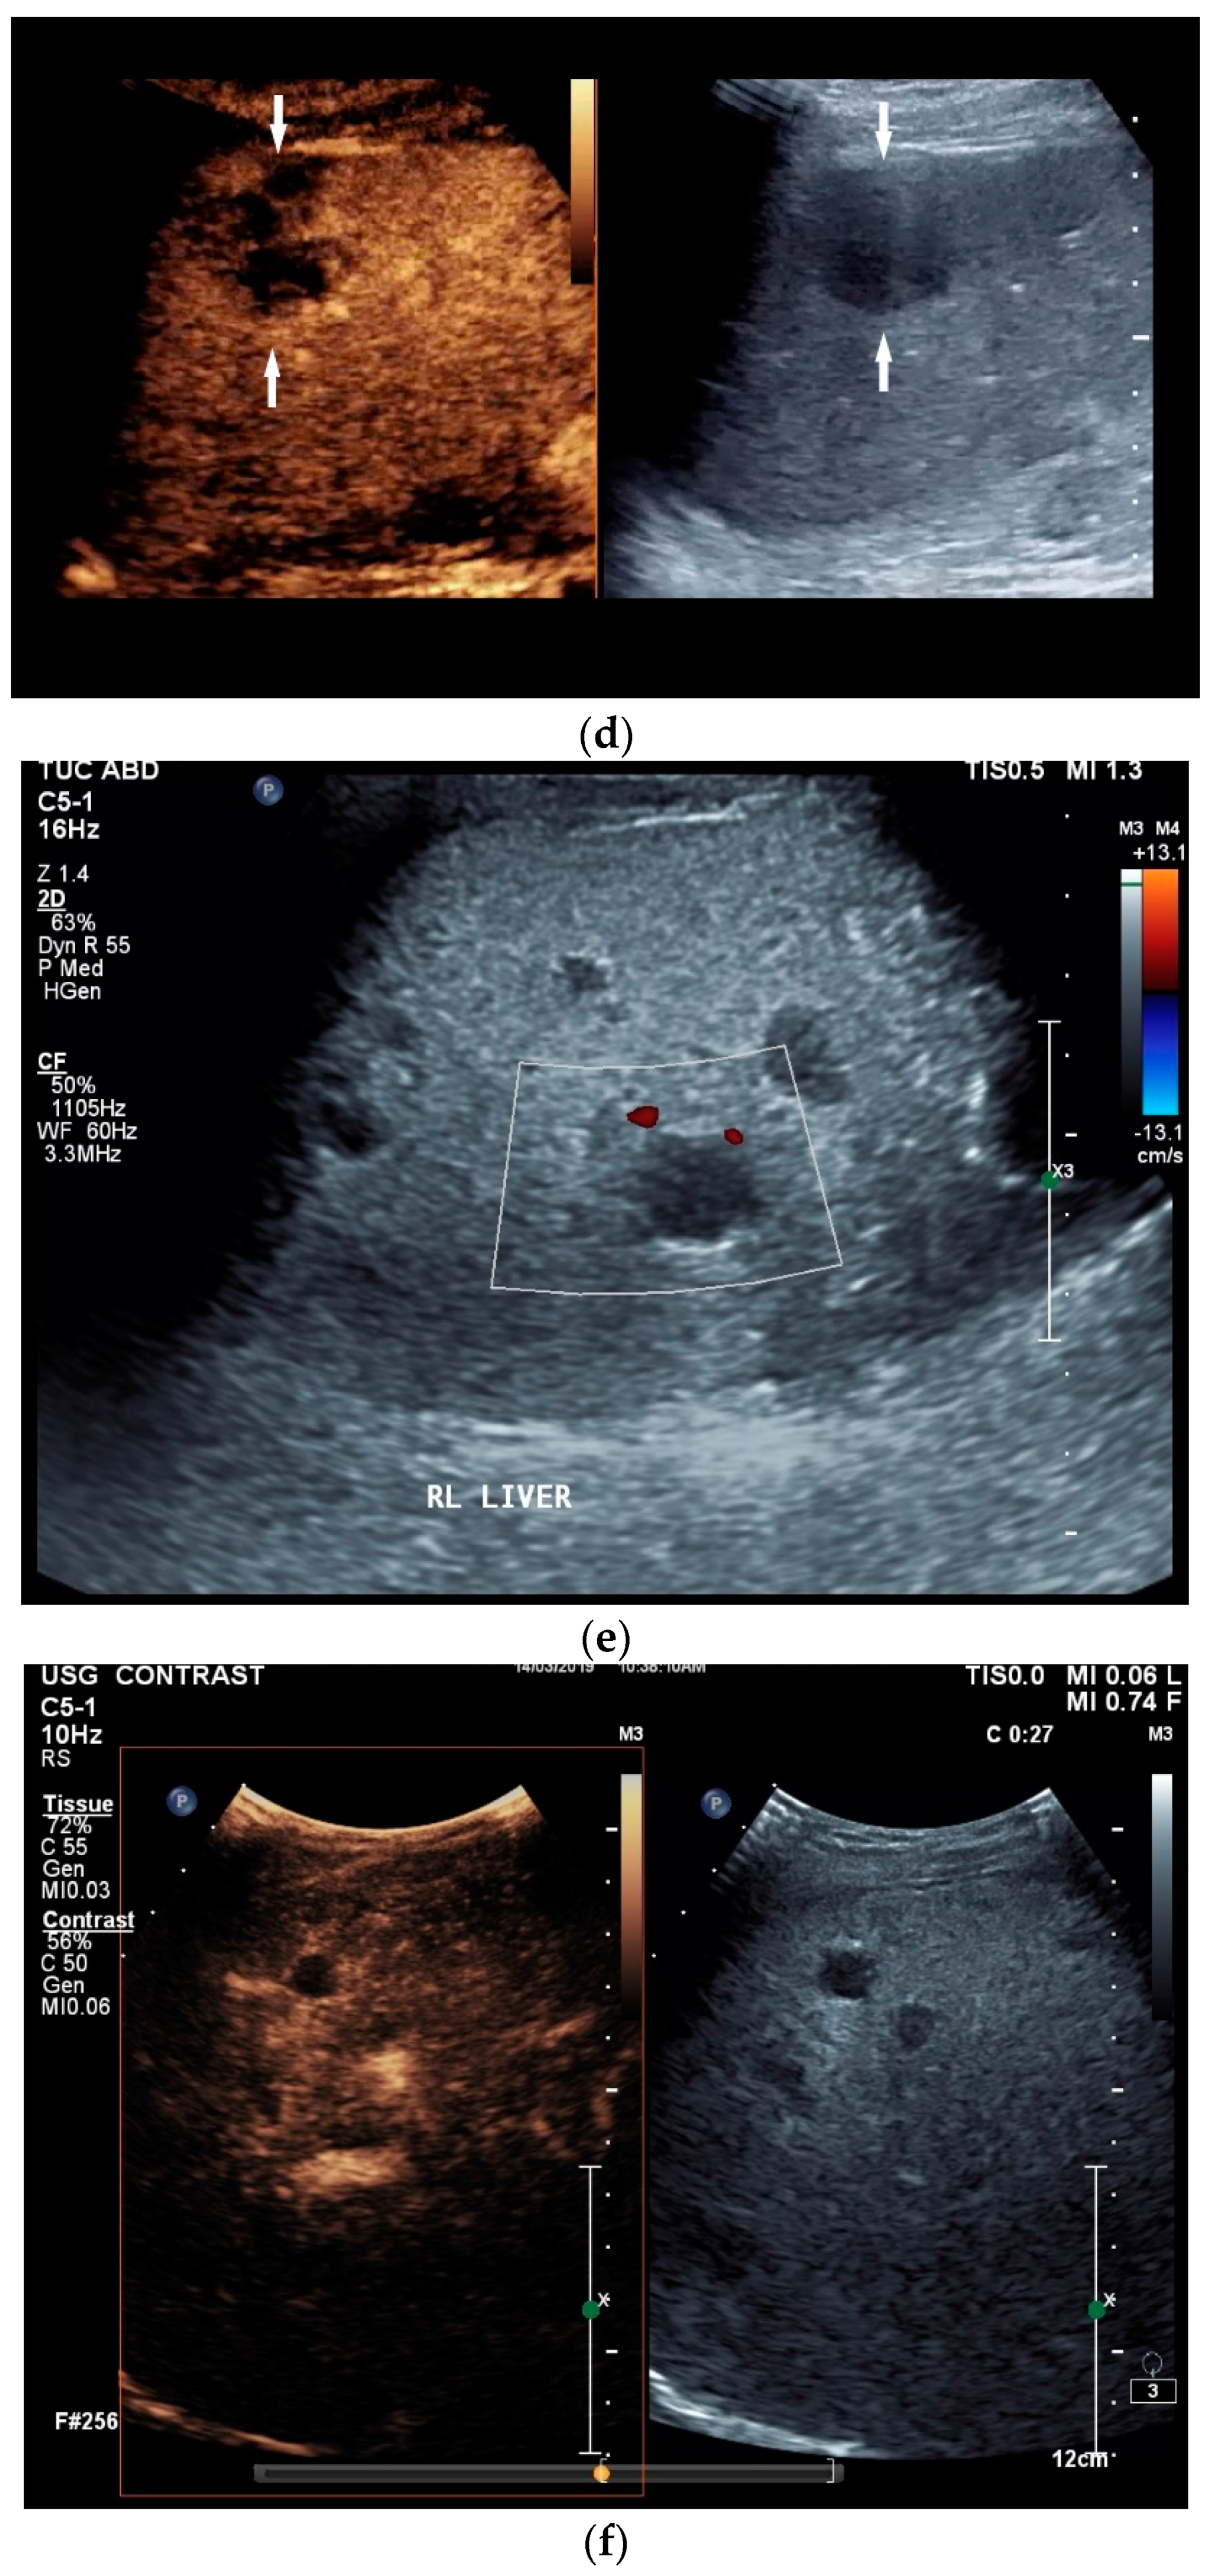

Figure 3.

Sonographic and CEUS features of hepatic tuberculosis. Subcapsular liver lesion (a); subcapsular liver lesions (white arrow) and hypoechoic lesion on the capsule (green arrow) using a linear transducer of 12 MHz (b). Caseous necrosis, histologically proven. Hypoechoic lesion with hyperechoic rim using B-mode ultrasound (right side of image). The lesion is hyperenhanced in the arterial phase at the edge of the CEUS; the center is nonenhanced with the exception of some enhanced septa (c). In the portal venous phase, the peripheral areas are hypoenhanced (d). Multiple small, smoothly bordered, non-cystic hypoechoic lesions in the liver, with no evidence of macrovessels when using Color Doppler Imaging (e). CEUS shows mild peripheral enhancement around the lesions. The lesions are without enhancement in the arterial phase (f), portal venous phase (g), and late phase (h).

The micronodular form is usually caused by hematologic seeding via the hepatic artery in disseminated disease. If the nodules are very small and cannot be delineated via ultrasound, hepatomegaly sometimes remains the only conspicuous finding from liver ultrasound, with possible manifestations in other organs.

The macronodular form is characterized by single tuberculomas or macronodular lesions. Seeding more likely often occurs from the gastrointestinal tract via the portal vein [54]. A focal or nodular form without extrahepatic tuberculosis manifestation is very rare [59].

Abscesses can develop from the caseous necrosis, but are rare [58]. The formation of a multiseptated liver abscess with numerous septa has also been described in a case study [60] [Figure 3c–g].

The morphological correlate of hepatic tuberculosis is granulomatous inflammation, characterized by central caseous necrosis with peripheral granulation tissue. Both melting abscesses and calcified nodules may occur in the course of the disease.

Ultrasound presents hypoechoic or isoechoic liver lesions [56]. Hyperechoic lesions are rarely described (although, these can be found in hepatitis B infections and hepatitis C-related liver cirrhosis; however, histologically confirmed cases have categorized these as tuberculoma related, and not as regenerative nodule or hepatocellular carcinoma (HCC)) [59,61]. Depending on the stage of the disease, the inflammatory lesions are homogeneously hyperenhanced via CEUS. Most lesions develop a washout in the portal venous phase. Melting abscesses show a hyperenhanced rim with either a hypoenhanced or nonenhanced center or a heterogeneous enhancement [62,63] [Figure 3c,d]. Vascular complications, such as portal vein thrombosis, have been caustically described and found to be in connection with hepatitis B [54,64].